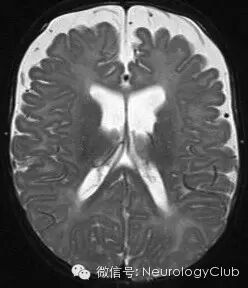

(1)梗阻性脑积水:头颅X线片为颅骨内板可见指压痕(慢性病例)。CT见脑室扩大,双额角径或颅内径(Evans指数)>0.33是诊断脑积水的标志性指标;额角变锐<100°颞角宽度>3mm;脑室边缘模糊,室旁低密度晕环;基底池,脑沟受压/消失。MRI为矢状位T1可显示导水管梗阻,幕上脑室扩大;胼胝体变薄,向上拉伸;穹窿、大脑内静脉向下移位、第三脑室底疝入扩大的蝶鞍。T2显示脑脊液样的指纹状高信号向脑室外延伸到脑组织,间质水肿在脑室角周围明显;脑室内脑脊液形成湍流;导水管流空消失。增强T1显示软脑膜血管淤滞,类似于脑膜炎改变。心电门控相位对比MRI电影为在导水管中无明显脑脊液流动。推荐影像学检查:3DCISS序列可减少脑脊液流动伪影,更好显示脑室轮廓及透明隔,心电门控相位对比MRI电影。

(图来自网络——小编注)

(2)正常压力脑积水:CT见脑室扩大伴额角变钝。MRI有脑室扩大;额角颞角扩大不伴海马萎缩;基底池、外侧裂扩大,脑沟正常;部分病例在质子密度像及常规自旋回波序列可消失导水管流空现象;脑脊液电影可消失脑脊液流速增加。推荐影像学检查是心电门控相位对比MRI电影。